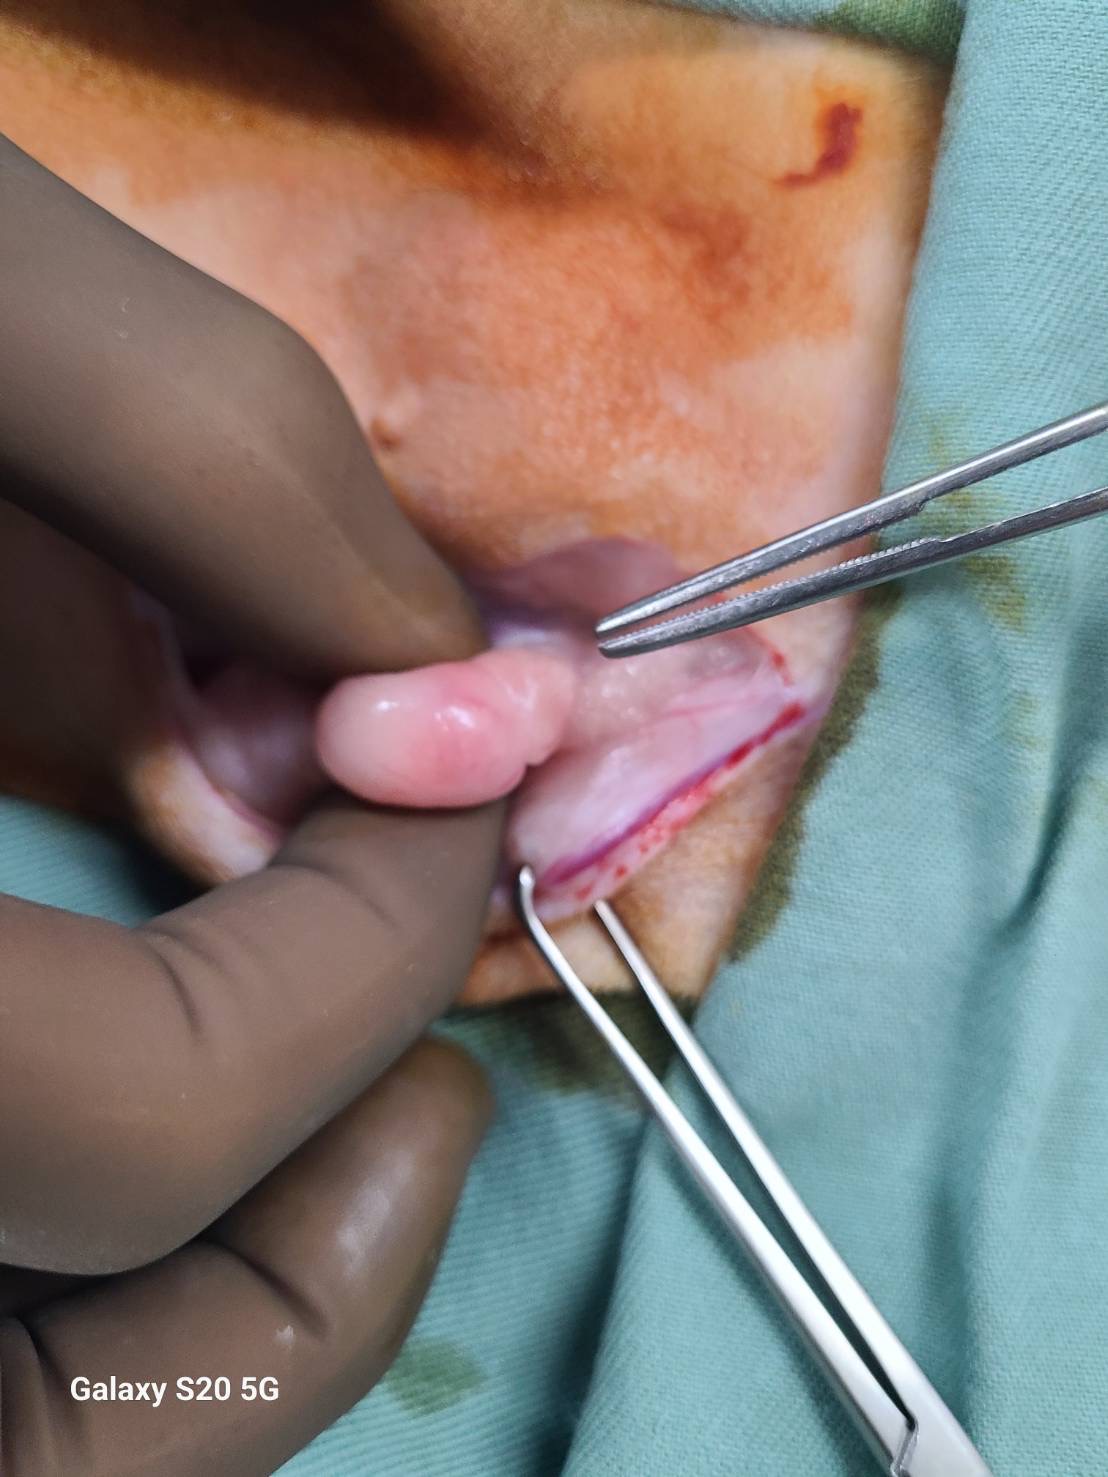

写真